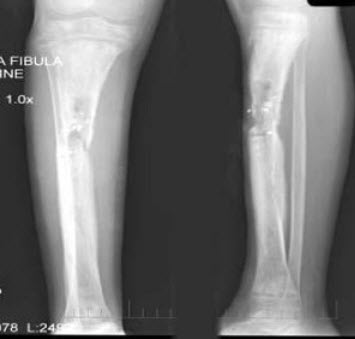

260、单项选择题

男,47岁,右小腿反复肿胀,摄片如图,考虑为慢性化脓性骨髓炎,下列描述错误的是()

A.骨干增粗,变形

B.骨髓腔变窄,消失

C.骨质以增生硬化为主

D.可见泥沙样死骨

E.以上均不正确